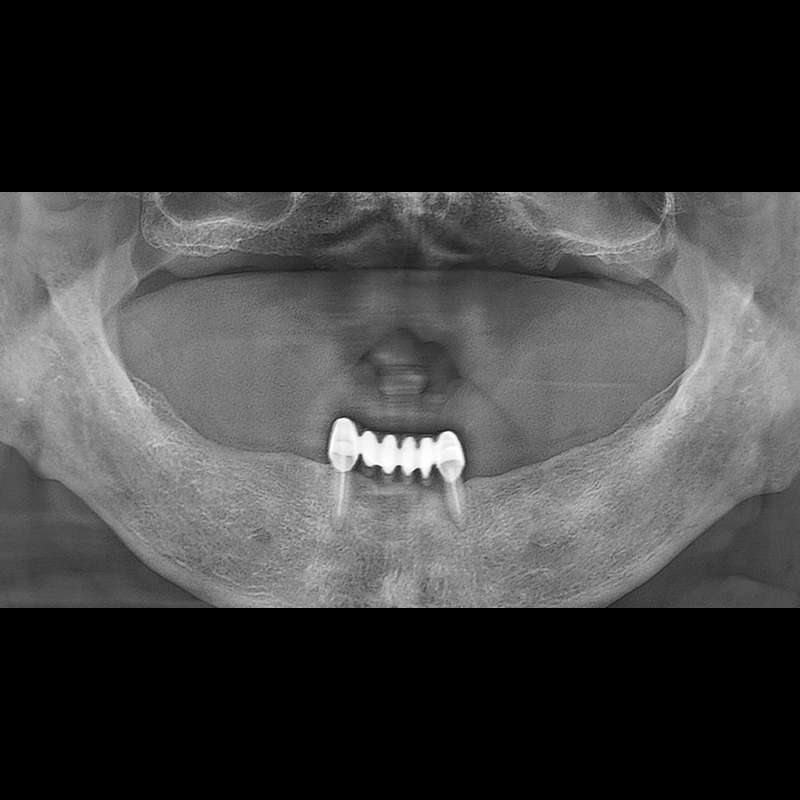

BEFORE AFTER

种植牙前后的照片 2025.05.30

在缺失的牙齿部分和难以挽救的牙齿位置植入了种植牙。